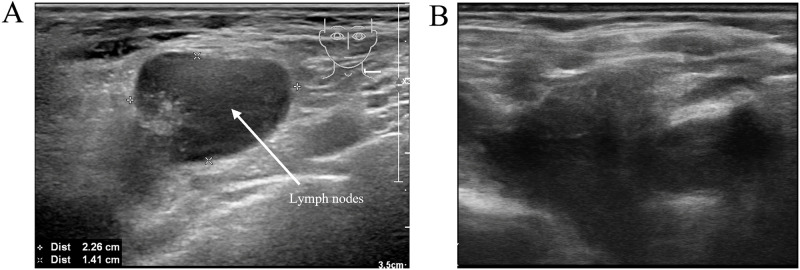

Post-transplant lymphoproliferative disorder (PTLD) is a rare complication following hematopoietic stem cell transplantation (HSCT), with its occurrence post-autologous hematopoietic stem cell transplantation (auto-HSCT) being even rarer. Research on PTLD following auto-HSCT is exceedingly scarce. Here, we present a noteworthy instance wherein a patient with diffuse large B-cell lymphoma (DLBCL) developed PTLD, manifesting as classical Hodgkin lymphoma (cHL) two years after auto-HSCT. Additionally, we conducted an extensive review of existing literature, exploring the current research on PTLD following auto-HSCT and illuminating this scarcely examined area.